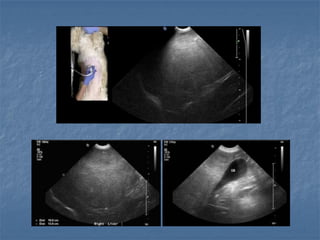

Obstrução Biliar Extra-Hepática (cães)

 Sinais de obstrução

Pesquisa da etiologia da obstrução/ compressão:

- Inflamatória (fígado, pâncreas e TGI)

- Cálculos

- Tumores (fígado, pâncreas, linfonodos, duodeno)

cálculos abscesso

DBC

gordura

pancreatite

colelitíase

colangiocarcinoma

colangite e pancreatiteInflamação pielogranulomatosa com fibrose